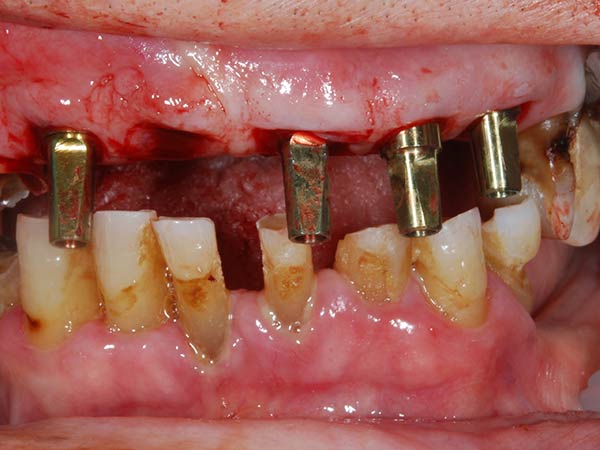

I denti irrecuperabili dell'arcata superiore ed inferiore del paziente di anni 65

sono stati sostituiti da 10 impianti, cioè protesi radicolari endo-ossee che sostengono le protesi fisse superiore ed inferiore.